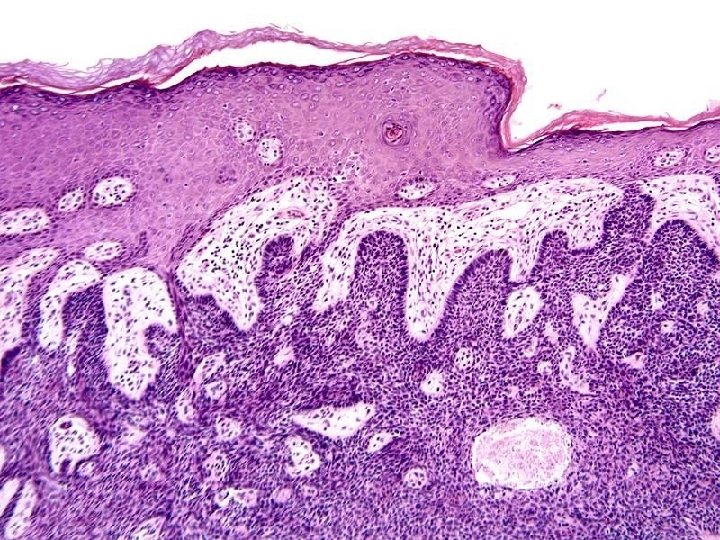

PSORIASIS • 1 -2% of USA • Elbows, Knees • Parakeratosis, generalized epidermal hyperplasia, elongation of the rete pegs, extensive chronic inflammatory cell infiltrates, “MUNRO” intraepidermal microabscesses